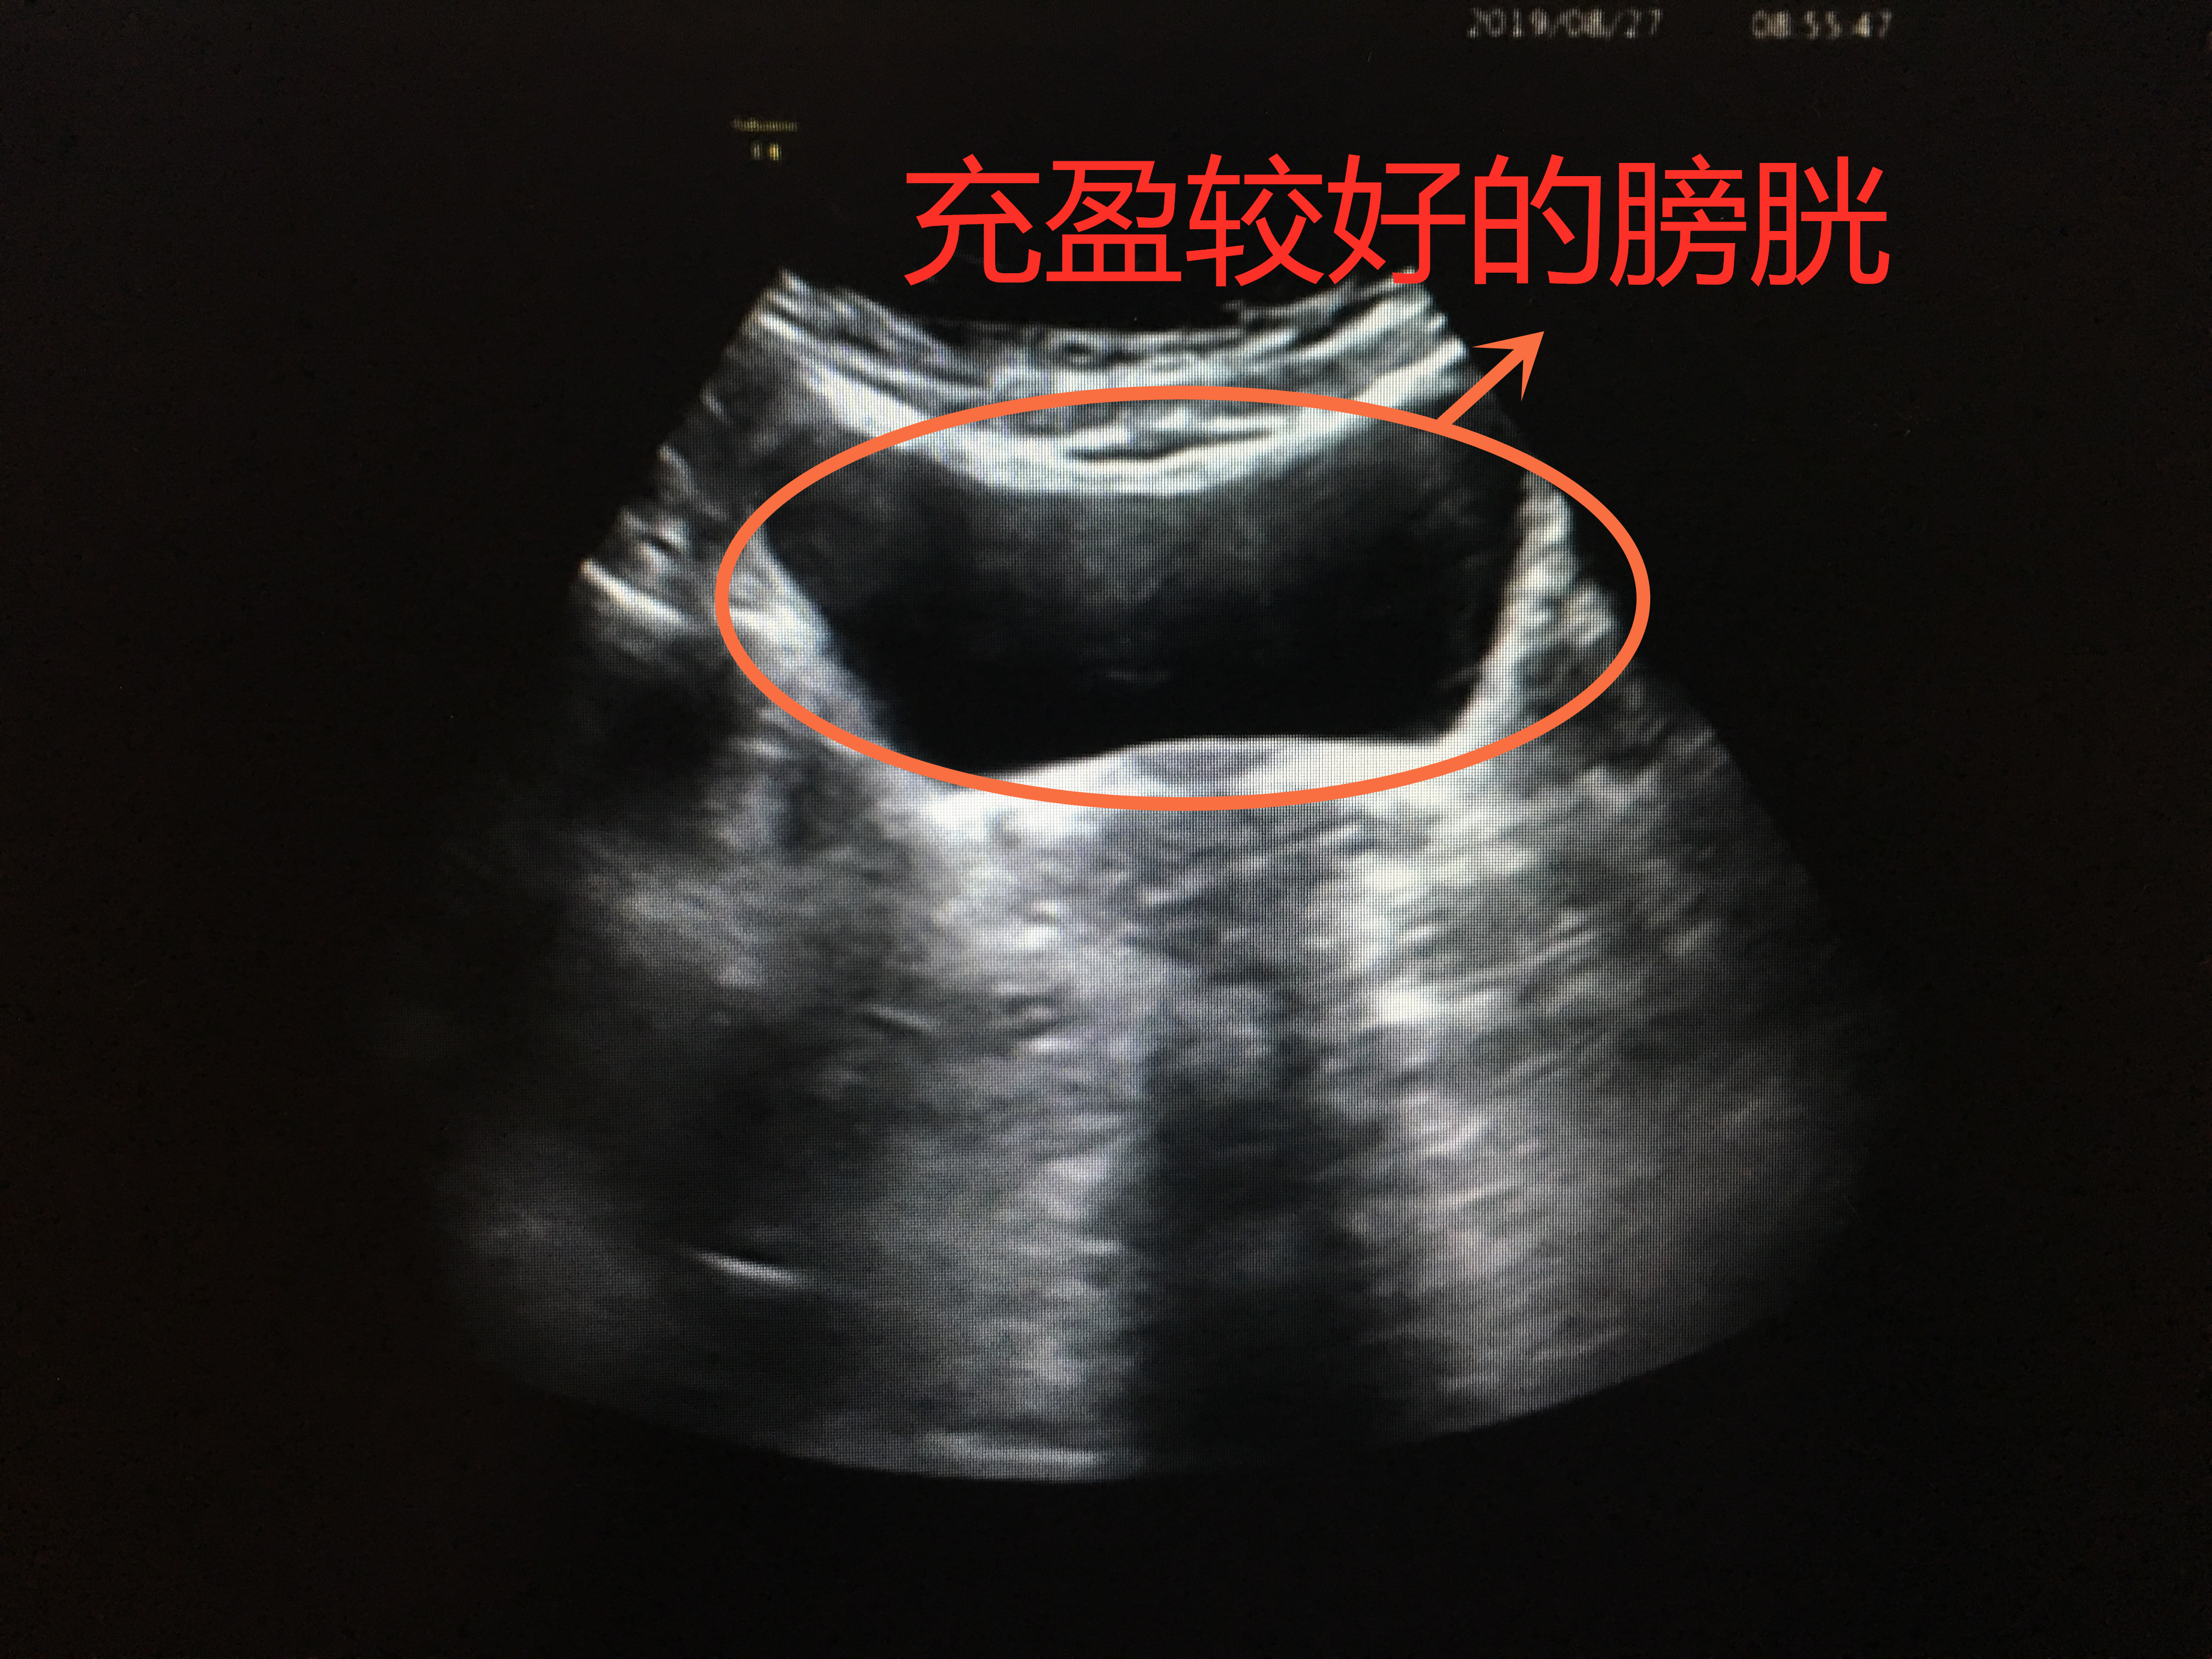

憋尿较好,膀胱充盈

膀胱就像一个皮球,当你往里面打足气时,皮球便充分撑开;而当打的气不够时,皮球就瘪着。所以,当你憋尿充足时,膀胱充盈起来,把每个角落都撑开,检查时便一览无遗;当憋尿不够,充盈欠佳时,局部可能皱褶起来,隐藏病灶。所以,下次医生让你憋尿的时候,就努力的憋吧。